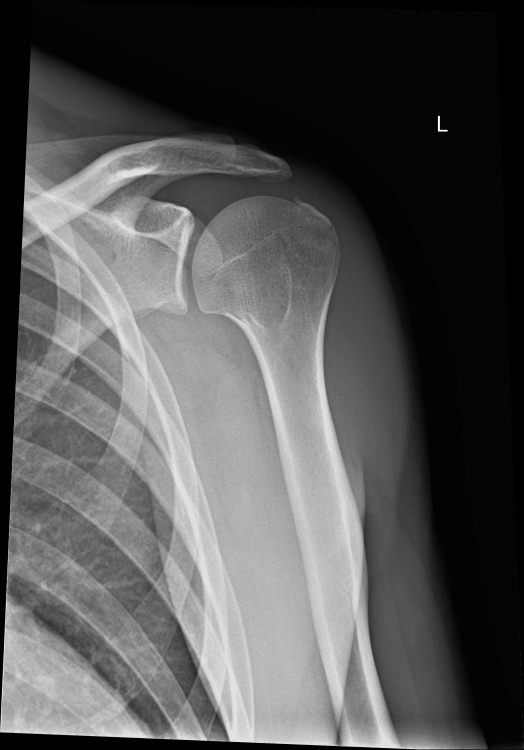

3. Röntgen am Unfalltag: --- MRT nach 6 Wochen (die Bilder habe ich selbst am PC gemacht - mein Arzt hat sie mir vorher gezeigt): --- Röntgen nach 12 Wochen: